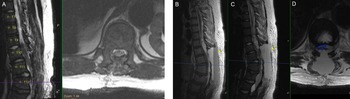

The patient underwent T9-L1 laminectomy for resection of intradural cysts and adhesions, fenestration of the multiloculated cysts, and detethering of the thoracic spinal cord at T9-T11. Pathology demonstrated benign intradural cysts. He was taken to the PICU and then to MRI for evaluation of any post-op fluid collection or blood at the surgical site (Figure 2A). The postoperative MRI showed no hematoma and excellent decompression of the spinal cord. Heparin infusion started 6 hours after surgery; aspirin and warfarin started on postoperative day (POD) one.

Figure 2: Postoperative findings of cord decompression and subsequent expansive epidural hematoma on T1-weighted sagittal and T2-weighted sagittal/axial thoracic MRI. (A) Postoperative day (POD) 0 imaging of T2-weighted sagittal/axial series showing cord decompression and detethering of the cord. (B–D) POD2 imaging of T1-weighted sagittal, T2-weighted sagittal, and T2-weighted axial series, respectively, showing distinct fluid level with massive layered epidural hematoma (yellow arrows) causing cord compression (blue outline).

The patient was ambulating on POD1. On POD2, he noted numbness and parasthesias in bilateral lower extremities and difficulty voiding but no weakness. STAT MRI was obtained (Figure 2B–D), and the patient was taken emergently to the operating room and lost bilateral extremity motor function en route. In surgery, he had a hematoma that spanned from T8 to L2 with significant compression of the cord and conus. The patient emerged from anesthesia with full strength in bilateral lower extremities and resolution of the numbness. Anticoagulation was resumed slowly 48 hours after this second intervention, first with a heparin infusion followed by aspirin (81 mg) and then warfarin. After stabilization, the patient was transferred from the ICU for ongoing rehabilitation, pain management, and anticoagulation titration.